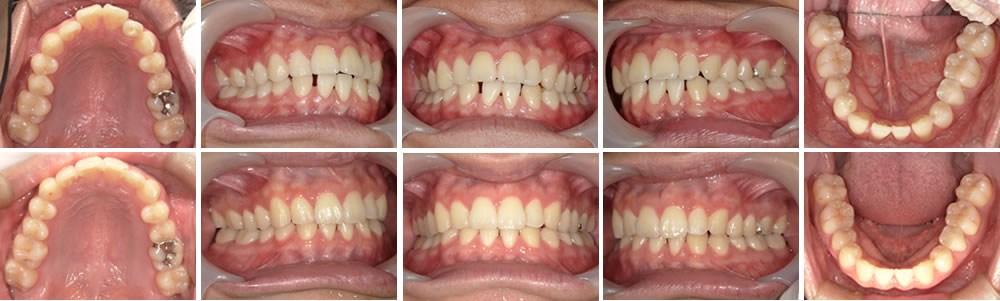

マウスピース矯正(インビザライン)で出っ歯と隙間を改善した症例

上の前歯の突出感が気になるということでインビザラインでの矯正治療をご希望された患者さまです。

下の前歯は側切歯が左右で1本ずつ先天性欠損のため、隙間が大きく開いており、歯石が溜まりやすい等の問題もあったため、隙間を埋めるよう設計しました。

治療後は一番気になっていた上の前歯の突出感も改善され、下の前歯の隙間もなくなり、上下でしっかりと噛み合うようになりました。